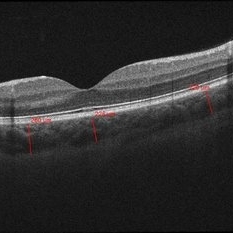

05- Unilateral Acute Idiopathic Maculopathy (UAIM) - OCT OD

20-year-old white, male presented for initial evaluation with one week history of acute, sudden, painless loss of central vision in his right eye a week prior to presentation. - H/O short course of exogenous testosterone, Tamoxifen and Clomiphene intake ~ 2-3 weeks cycle, which was already stopped, prior to development of pt's symptoms. - H/O acute illness with generalized fatigue, malaise, URTI like symptoms and rash over the hands and chest, just prior to symptoms development, and upon further discussion, pt mentioned that few of his friends got sick around the same time. - Patient was seen the week prior by general ophthalmologist and was found to have SRF on OCT , diagnosed with CSCR and referred for retina evaluation. - ROS/ PMHx: Negative, healthy aside from the short illness described above - Denied any prior vision problems, similar episodes, trauma etc - VA Dsc OD: 20/400 OS:20/20 - anterior segment exam - unremarkable - posterior segment - macular RPE changes/ clumping with GA with no CME/ SRF or crystals OD, and unremarkable OS. - Pseudocolor and FAF photos: RPE changes/ clumps w/ GA and stippled autofluorescense OD, unremarkable OS. - HD SD-OCT: thickened choroid, thickened/ hypertrophied subfoveal RPE with hyper-reflective material on the apical side of the retinal pigment epithelium/apical debris, Subfoveal ellipsoid zone atrophy w/ intact ELM W/No CME or SRF OD, Unremarkable OS. - FA: Dye not available - ICG: deferred - mf-ERG & VF - patient rescheduled

Imaging device: Zeiss-Cirrus 4000

Condition/keywords: unilateral acute idiopathic maculopathy